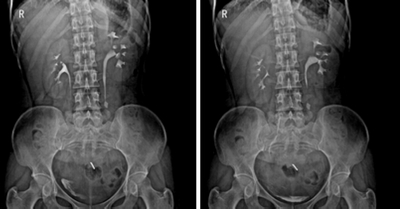

全面兼顧骨關(guān)節(jié)、呼吸、消化及生殖泌尿臨床檢查功能,同時實現(xiàn)數(shù)字化攝影功能、數(shù)字化透視功能、數(shù)字化胃腸功能、數(shù)字化造影功能、及介入放射影像成像等檢查(如透視下定位、透視下穿刺)。

★各種普通及特殊造影,如口服膽囊造影、靜脈膽道造影、T管造影、逆行胰膽管造影(ERCP)、靜脈腎盂造影(IVP)、子宮輸卵管造影、脊髓造影等。